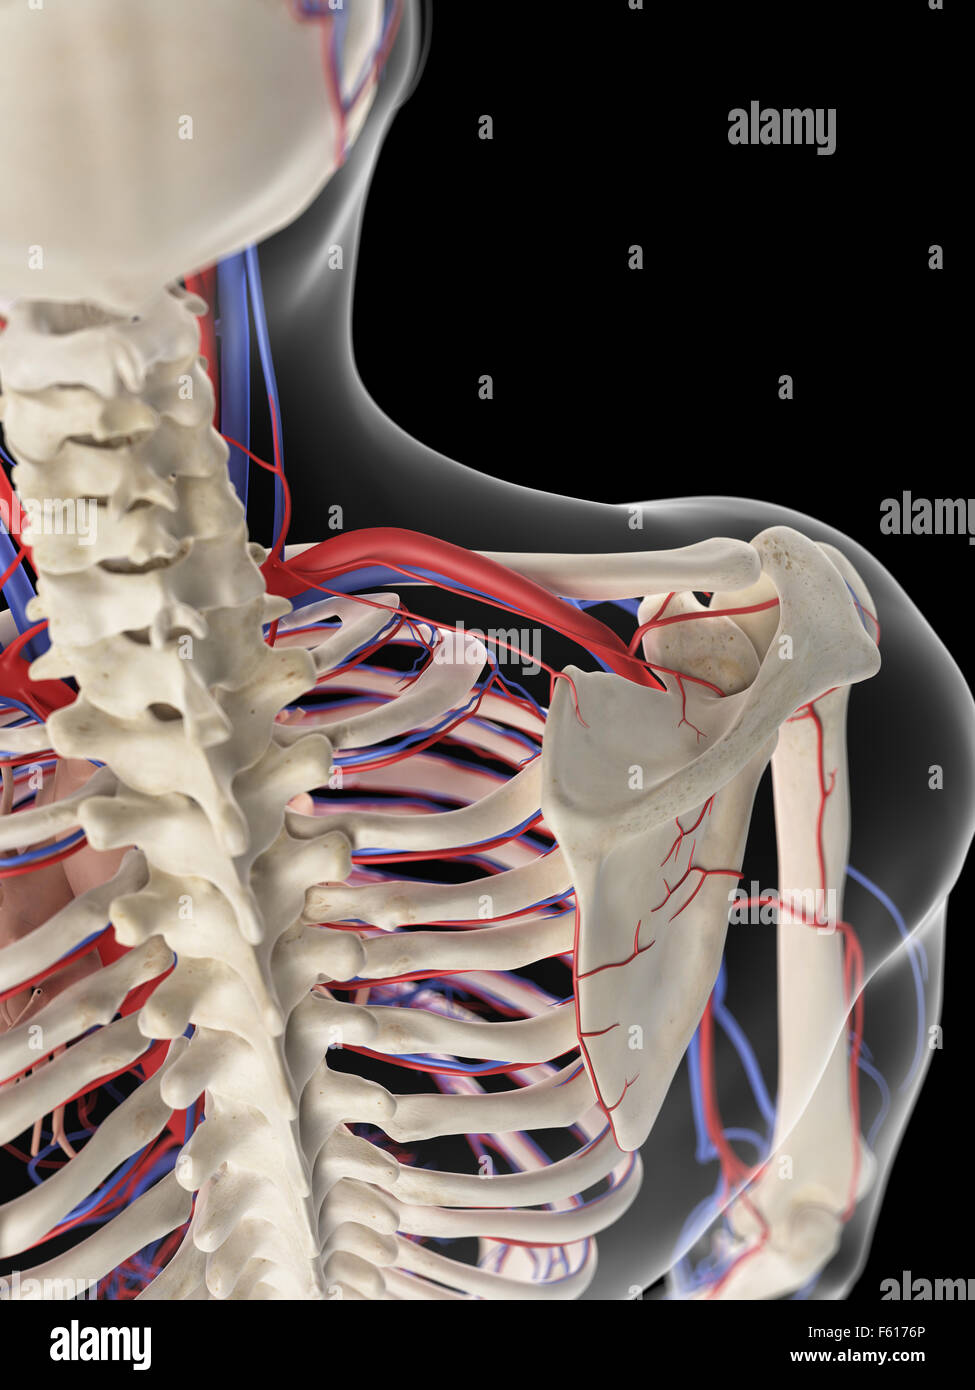

RMETMN27–Darstellung der Blutversorgung und Skelett-Struktur der Unterschenkel, durch die Haut sichtbar.

RMETMNMF–Darstellung der Blutversorgung und Skelettsystem an den Unterschenkeln, durch die Haut sichtbar.

RMETMP9E–Darstellung der Blutversorgung und Skelett-Struktur der Unterschenkel, durch die Haut sichtbar.